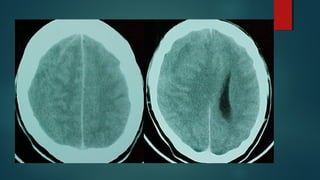

Este documento es el programa para un taller de imágenes del curso de emergencia 2015 impartido por el Dr. Víctor Delgado. El taller se centra en el uso de imágenes médicas para el diagnóstico y tratamiento de pacientes en coma traumático según la base de datos de Marshall. El Dr. Delgado es el único instructor repetido a lo largo del documento.